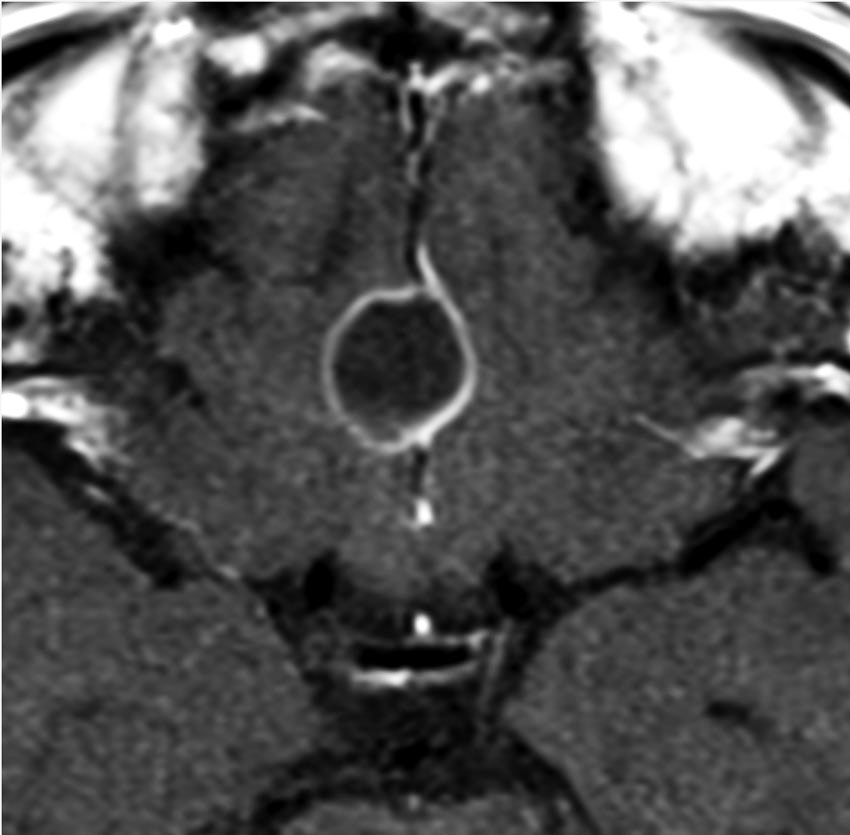

成人の第3脳室内部に局在する頭蓋咽頭腫です。経脳梁法で両側のモンロー孔から全摘出しました。下垂体組織は残っています。これは乳頭状頭蓋咽頭腫と呼ばれるもので,成人にしか発生しません,のう胞がなく石灰化もないのが大きな特徴です。境界が明瞭で柔らかく摘出が簡単なタイプとして知られています。この患者さんも術後に下垂体機能不全も視床下部障害も生じませんでした。